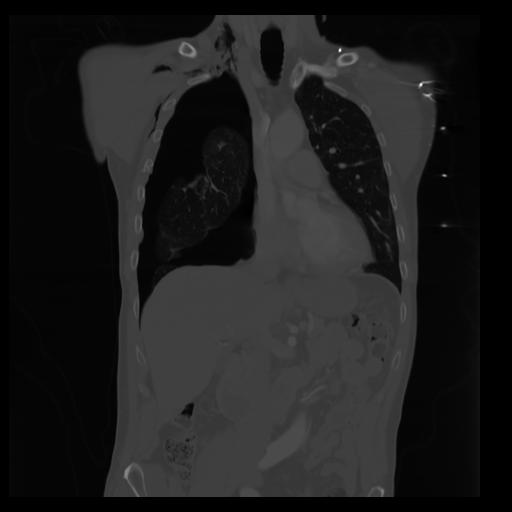

29 CUERPO,CE,Coronal,3.000,CUERPO,Coronal,